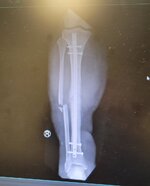

I thought the bike looked bad until your leg popped up. Wow! I pray you heal well.

The bike is about 2500 in parts I might fix it next year only 4000 miles on it. The wife is PISSED and said she will never get on a bike again she said she has PTSD now just glad she was not on it.. me at 65 with a bad leg now mabey a Can Am spyder.

Just let me know, I have a the original shifter set up and mufflers and seat that were taken off at 1500, the TOR on the right just got scratched, sand paper and repowder coat will fix, also got the cross over pipe on it. Someone is going to get a deal, really would not take much. Hell it's got brand new tires with 100 yds on them:) be riding since I was 11, 65 now and if it was not for the accident I would have been riding for a long time to come

They did not total it they gave me 7200.00 to fix it! I was happy as hell, now If I took it to the shop at 100.00 an hour it would have taken the 7200

and more . So I looked around and about 2500.00 fixes it without the shop labor.